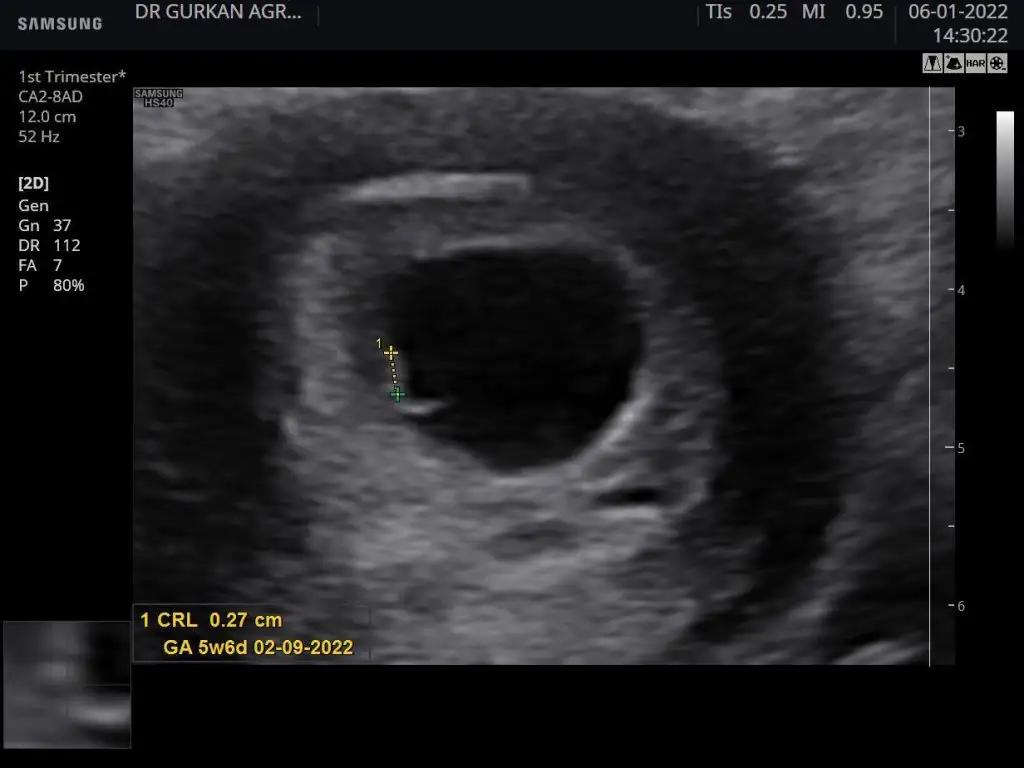

Kızlar bu bebiş doğdu eski usg si bu karından çekildi sizce kızmı erkek mi. Bakalım ramzi tutuacakmı

Eklentiler

• 0DCEF50D-ACE6-4185-8097-6F4BE314F73F.webp

41,6 KB · Görüntüleme: 74

• F171D4CC-1C2D-471D-8781-B2D9429E59F7.webp

21,8 KB · Görüntüleme: 79

• 14C4C8ED-DA59-4461-A23B-D4F4C45BBCF8.webp

22,9 KB · Görüntüleme: 70